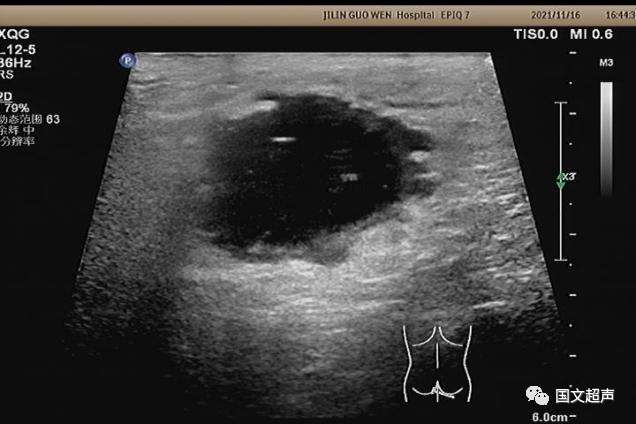

超聲檢查所見(jiàn):

肛周:7點(diǎn)鐘方向皮下脂肪層內(nèi)探及不均質(zhì)低無(wú)回聲包塊,范圍約4.6*3.0cm,較淺處距體表約0.6cm,邊界不清,周圍軟組織回聲增強(qiáng),CDFI:周邊血流信號(hào)豐富,輕加壓探頭有涌動(dòng)感,如下圖: